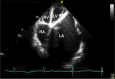

Giant Left Atrium Causing Dysphagia